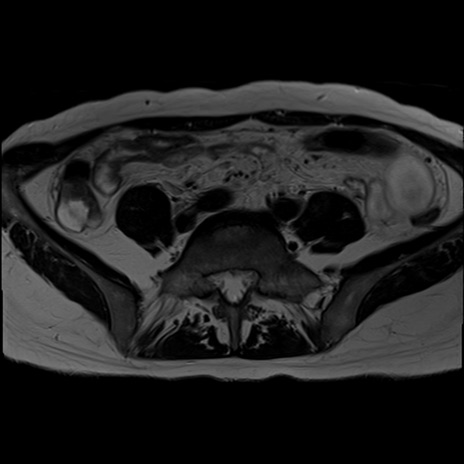

症例39 T2WI(横断像)

MRI(4日後)